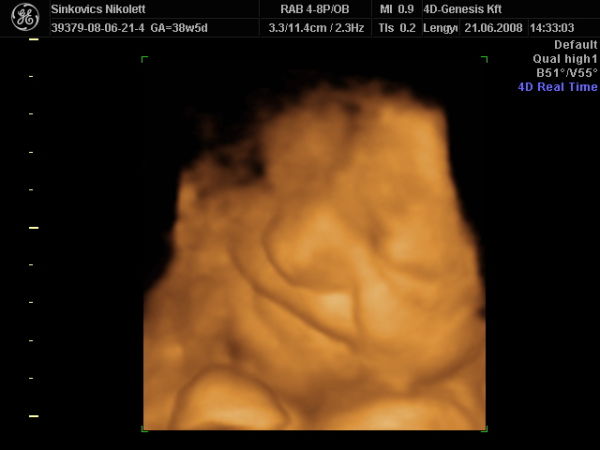

De majd ma, a Genesisben talán megmondják, hogy áll a méhlepény érettsége.